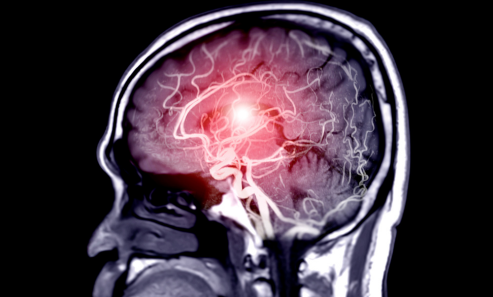

An aneurysm is an abnormal bulge or ballooning in the wall of a blood vessel. It occurs when the vessel wall weakens, causing it to expand under pressure. If left untreated, an aneurysm can rupture, leading to life-threatening internal bleeding or stroke.

Occurs in the blood vessels of the brain.

Can cause stroke or subarachnoid hemorrhage if it ruptures.